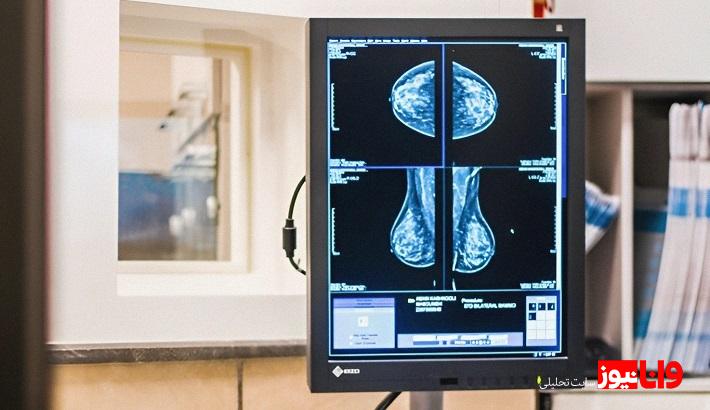

ماموگرافی چیست؟

در حقیقت این معاینه یک روش تصویربرداری پزشکی است که به وسیلهی اشعه ایکس انجام میشود و برای تشخیص و غربالگری زودهنگام سرطان سینه استفاده میشود. این روش به پزشکان کمک میکند تا تودههای کوچکی را که با معاینه فیزیکی قابل تشخیص نیستند، شناسایی کنند. در ادامه به بررسی جنبههای مختلف ماموگرافی، از جمله کاربردها، انواع، فرآیند، و ملاحظات خاص میپردازیم.